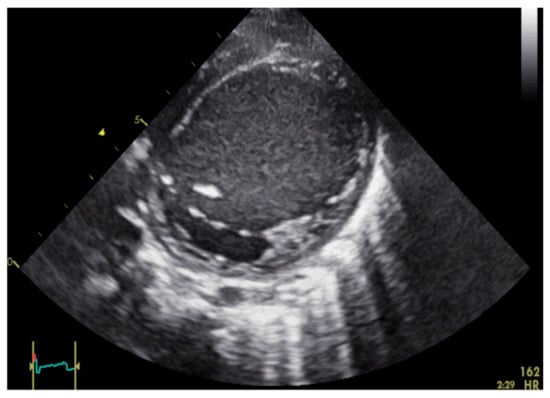

| Echocardiographic Parameters (Echo) | Left ventricular end-diastolic diameter (LVEDD) |

| LV EF, optional RV- EF | |

| Velocity time integral aortal and pulmonal (VTI’s) | |

| LVEDV, LVESV-RT3DE | |

| dp/dt MI (Mitral insufficiency), TAPSE | |

| Deformation parameter with speckle tracking method (ST) | |